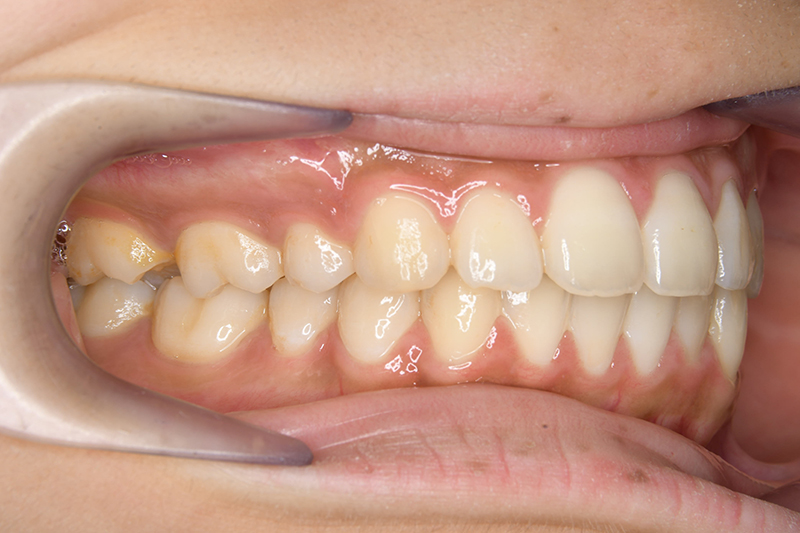

動的治療終了時

FP・IOP

批評・予后 上顎前歯舌側移動により上口唇形態は改善したこと、また動的治療中の下顎骨、特に下顎枝の成長が認められ下顔面高さは高くなったことが相俟って良好なプロファイルは得られたと思う。咬合の緊密化や歯根のパラレリングは行えたように思う。今後は第三大臼歯の萌出方向に注意を払い、頃合いを見計らって抜歯を検討している。

リスク 通院間隔が長くなったり顎間ゴムの協力が得られないと予定の治療期間より延長したり仕上がりが不十分になる恐れがあります。

ブラッシングを怠ると虫歯のリスクが高くなります。